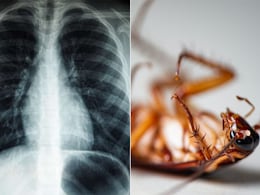

सांस लेने में हो रही थी दिक्कत, जांच में जो मिला, देख उड़े डॉक्टरों के होश, कॉकरोच ने फेफड़ों में बना लिया था घर!

किसी के फेफड़ों में कॉकरोच फंसने के कारण सांस लेने में समस्या होना बहुत दुर्लभ है. उन्होंने यह भी शेयर किया कि ऐसी घटनाएं लापरवाही के कारण हो सकती हैं.

सांस लेने में हो रही थी दिक्कत, जांच के बाद डॉक्टर्स भी रह गए शॉक्ड, फेफड़े में फंसा था 4 सेमी लंबा कॉकरोच

डॉक्टरों की एक टीम के उस वक्त होश उड़ गए, जब उन्होंने सांस लेने में तकलीफ की शिकायत पर अस्पताल पहुंचे एक मरीज की जांच की. पढ़ें क्या है पूरा माजरा.